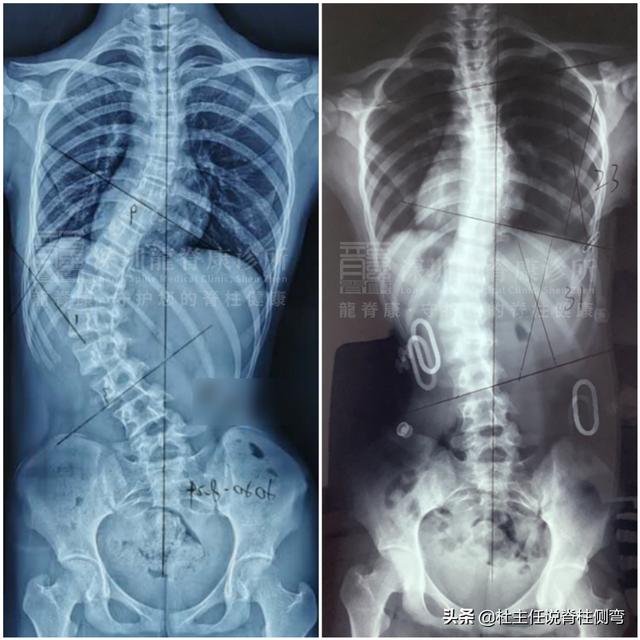

脊柱侧凸治疗案例。

因此,生长激素治疗前后每6-12个月进行一次全脊柱X线检查,以诊断胖乎乎威利患者的脊柱侧弯类型,并确定是否需要进行矫形治疗。

一般对这类患者的临床治疗原则是通过佩戴支具,结合骨科体操训练,限制脊柱侧弯的进展,避免手术治疗。